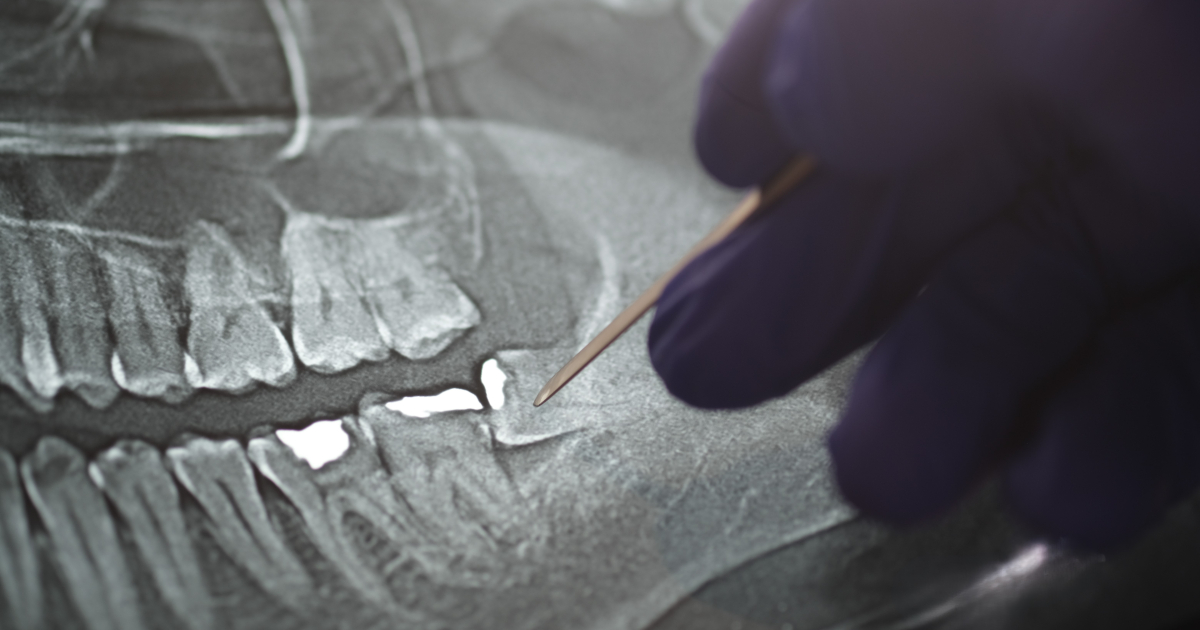

Panoramic Xray tooths showing Amalgam that used for dental restorative material

Image at top

Panoramic Xray shows amalgam used for dental restorative material. Istock/Getty